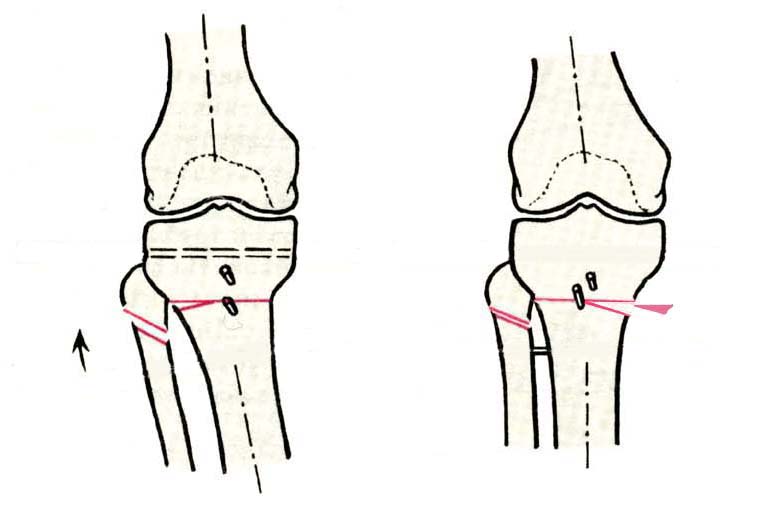

Дополнительными методами диагностики являлось измерение внутрикостного давления в зоне гипернагрузки и радионуклидные исследования нуклидами технеция. Применялись различные варианты остеотомий на различных сегментах. Для коррекции варусной-торсионной деформации:

высокие плюс, минус остеотомии большеберцовой кости,косая остеотомия малоберцовой. Для коррекции вальгусной деформации применялась плюс, минус надмыщелковая остеотомия бедренной кости. Фиксацию при высокой подмыщелковой остеотомии производили уникальной клинковой пластиной и тяговыми кортикальными винтами. Угол коррекции выставлялся

специальным угломером и направителем.

GBS> варусной-торсионной деформации: высокие плюс, минус остеотомии

GBS> большеберцовой кости,косая остеотомия малоберцовой.

Плюс, минус - это при одной операции? В смысле, и иссекали небольшой клин, и оставляли открытый с другой стороны?

GBS> остеотомии производили уникальной клинковой пластиной и тяговыми

GBS> кортикальными винтами. Угол коррекции выставлялся специальным

GBS> угломером и направителем.

В зависимости от баланса связок, комбинировали (+-)остеотомии или производили полную

минус или плюс остеотомию